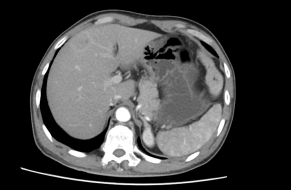

治疗后复查肝脏CT图片

蔡##,男,53岁,2013.6.22因“1.直肠癌 2.右肝转移癌”入住我科,于2013.06.26行“CT引导下肝转移瘤射频消融术”,2013.06.27在全麻下行“腹腔镜下直肠癌切除术+横结肠造瘘术+左侧睾丸鞘膜翻转术”,术后病理PT4N2M1,术后恢复顺利,并予继续化疗等综合治疗,现定期门诊复查,未见复发转移,一般情况良好,生活质量高。

治疗前肝转移CT图片